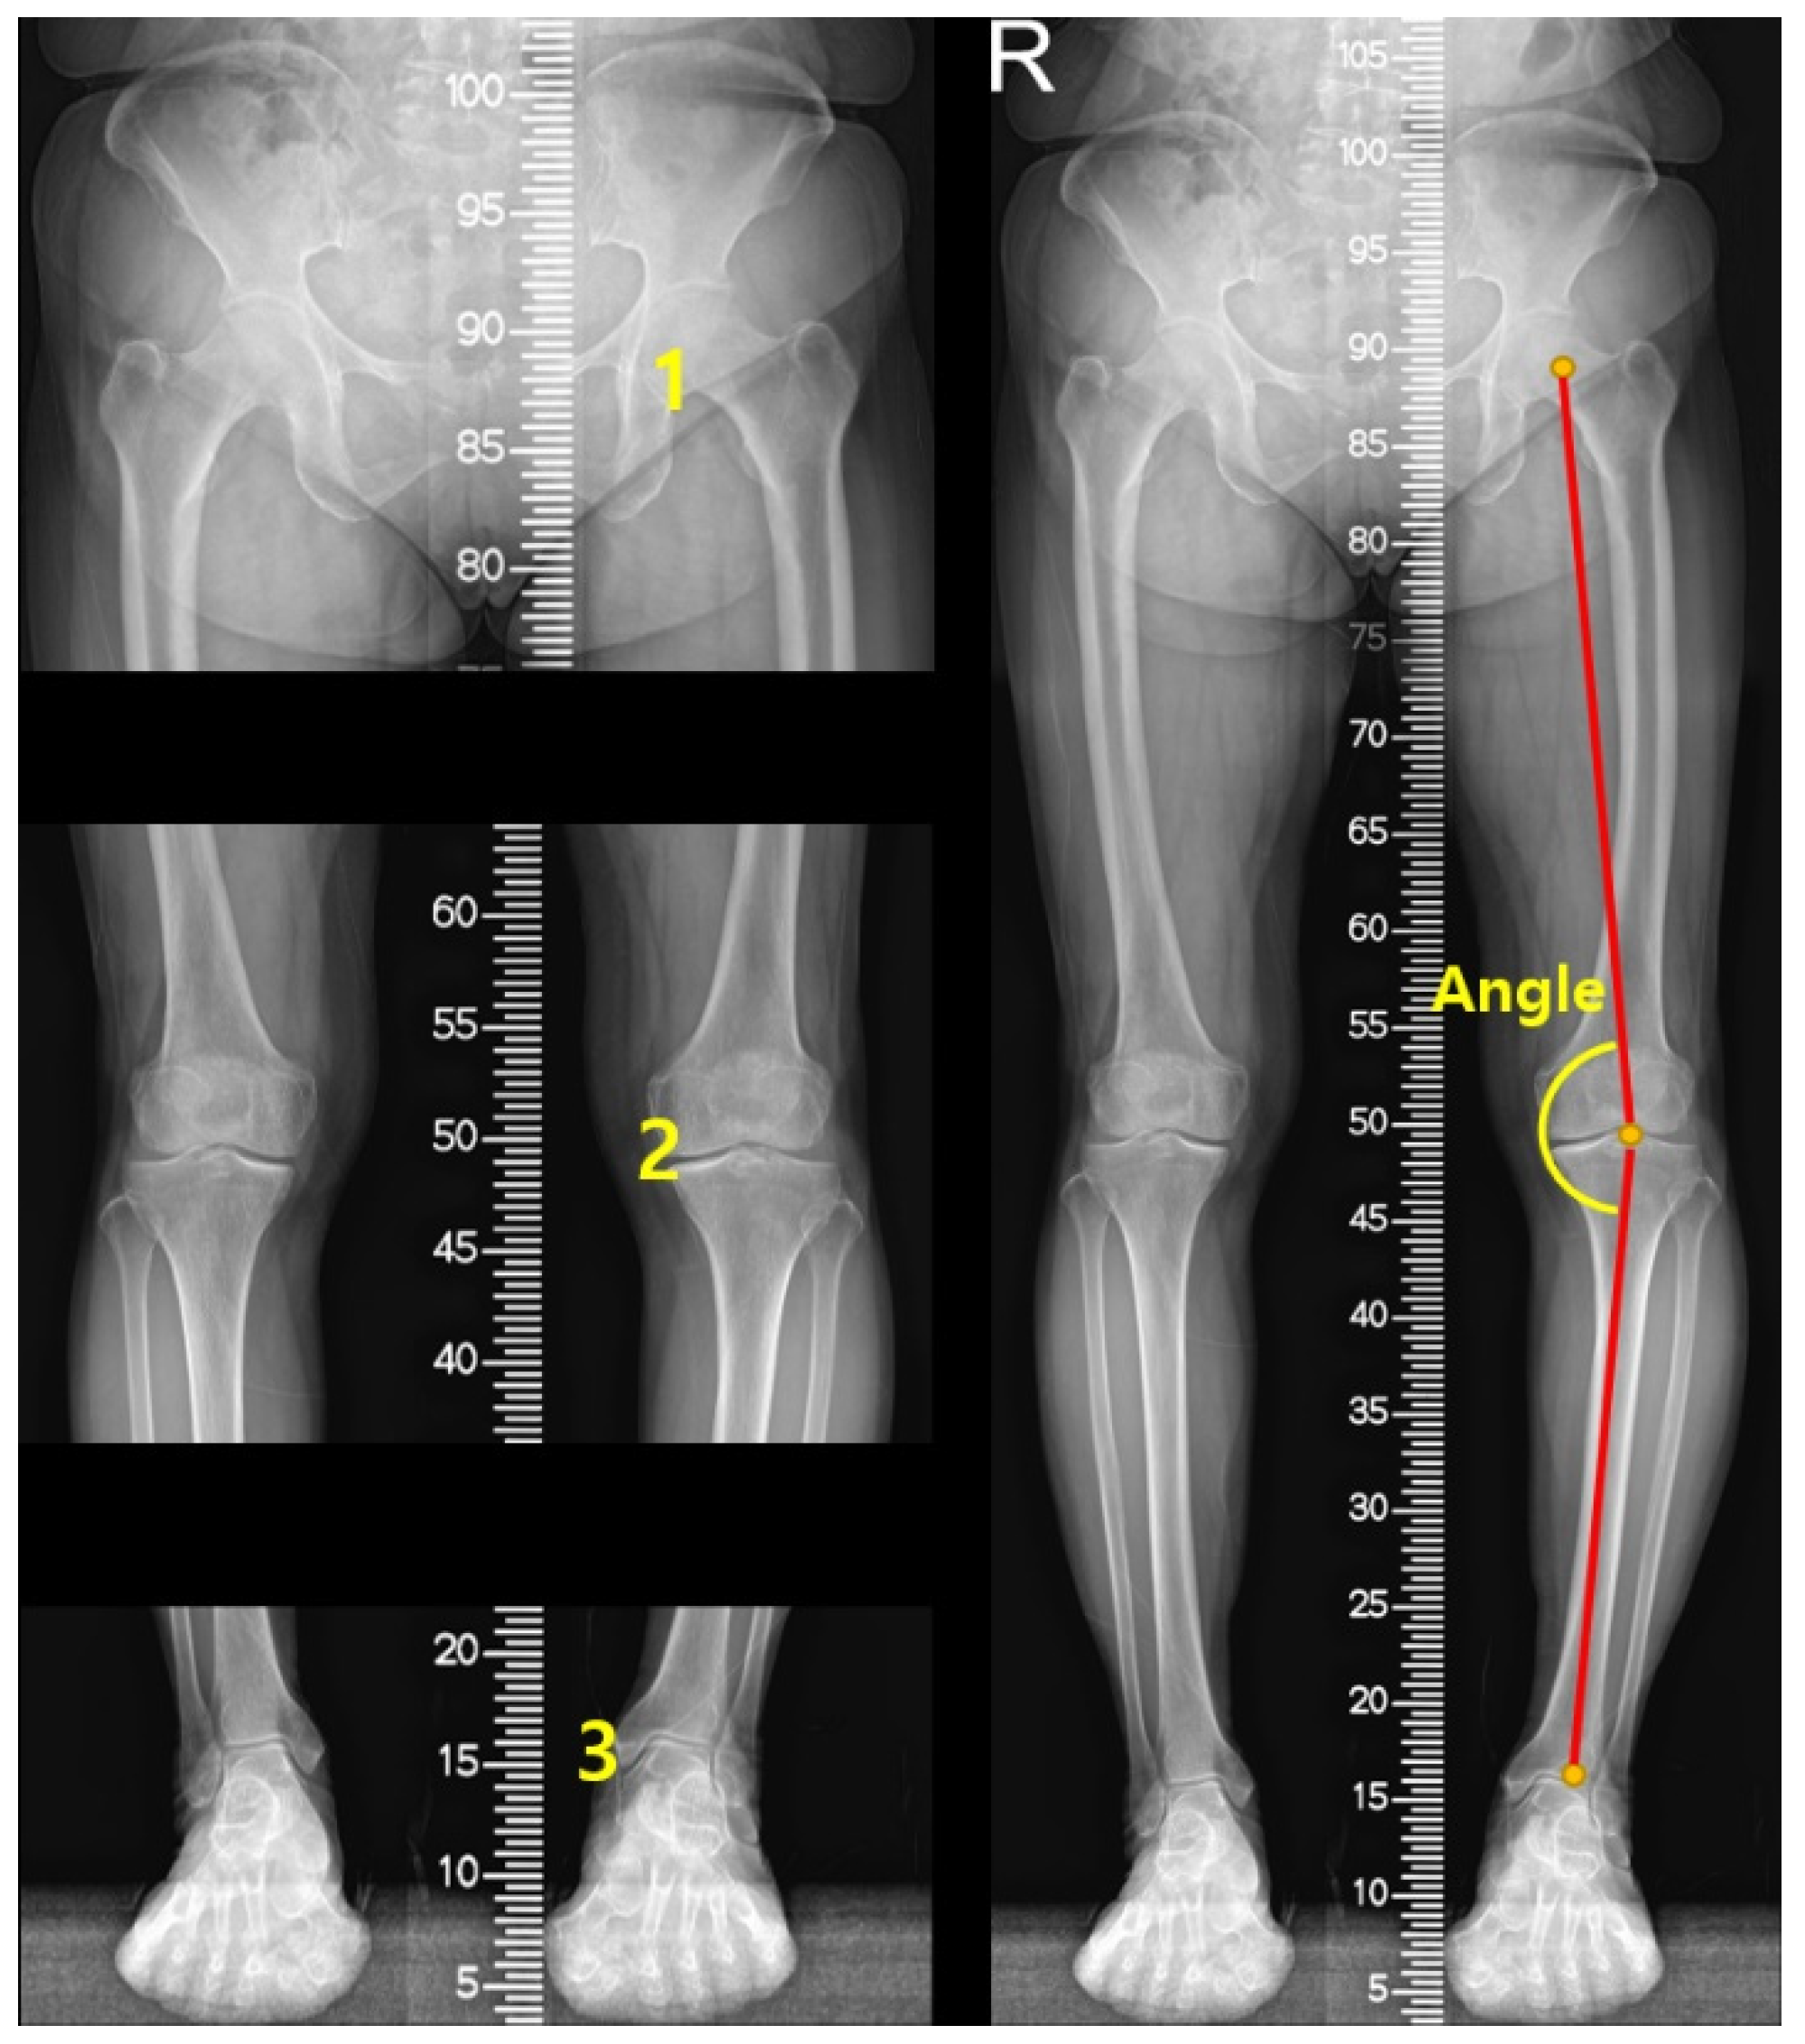

2.3.1. Measurement of the Lower Extremity Alignment on Radiographs